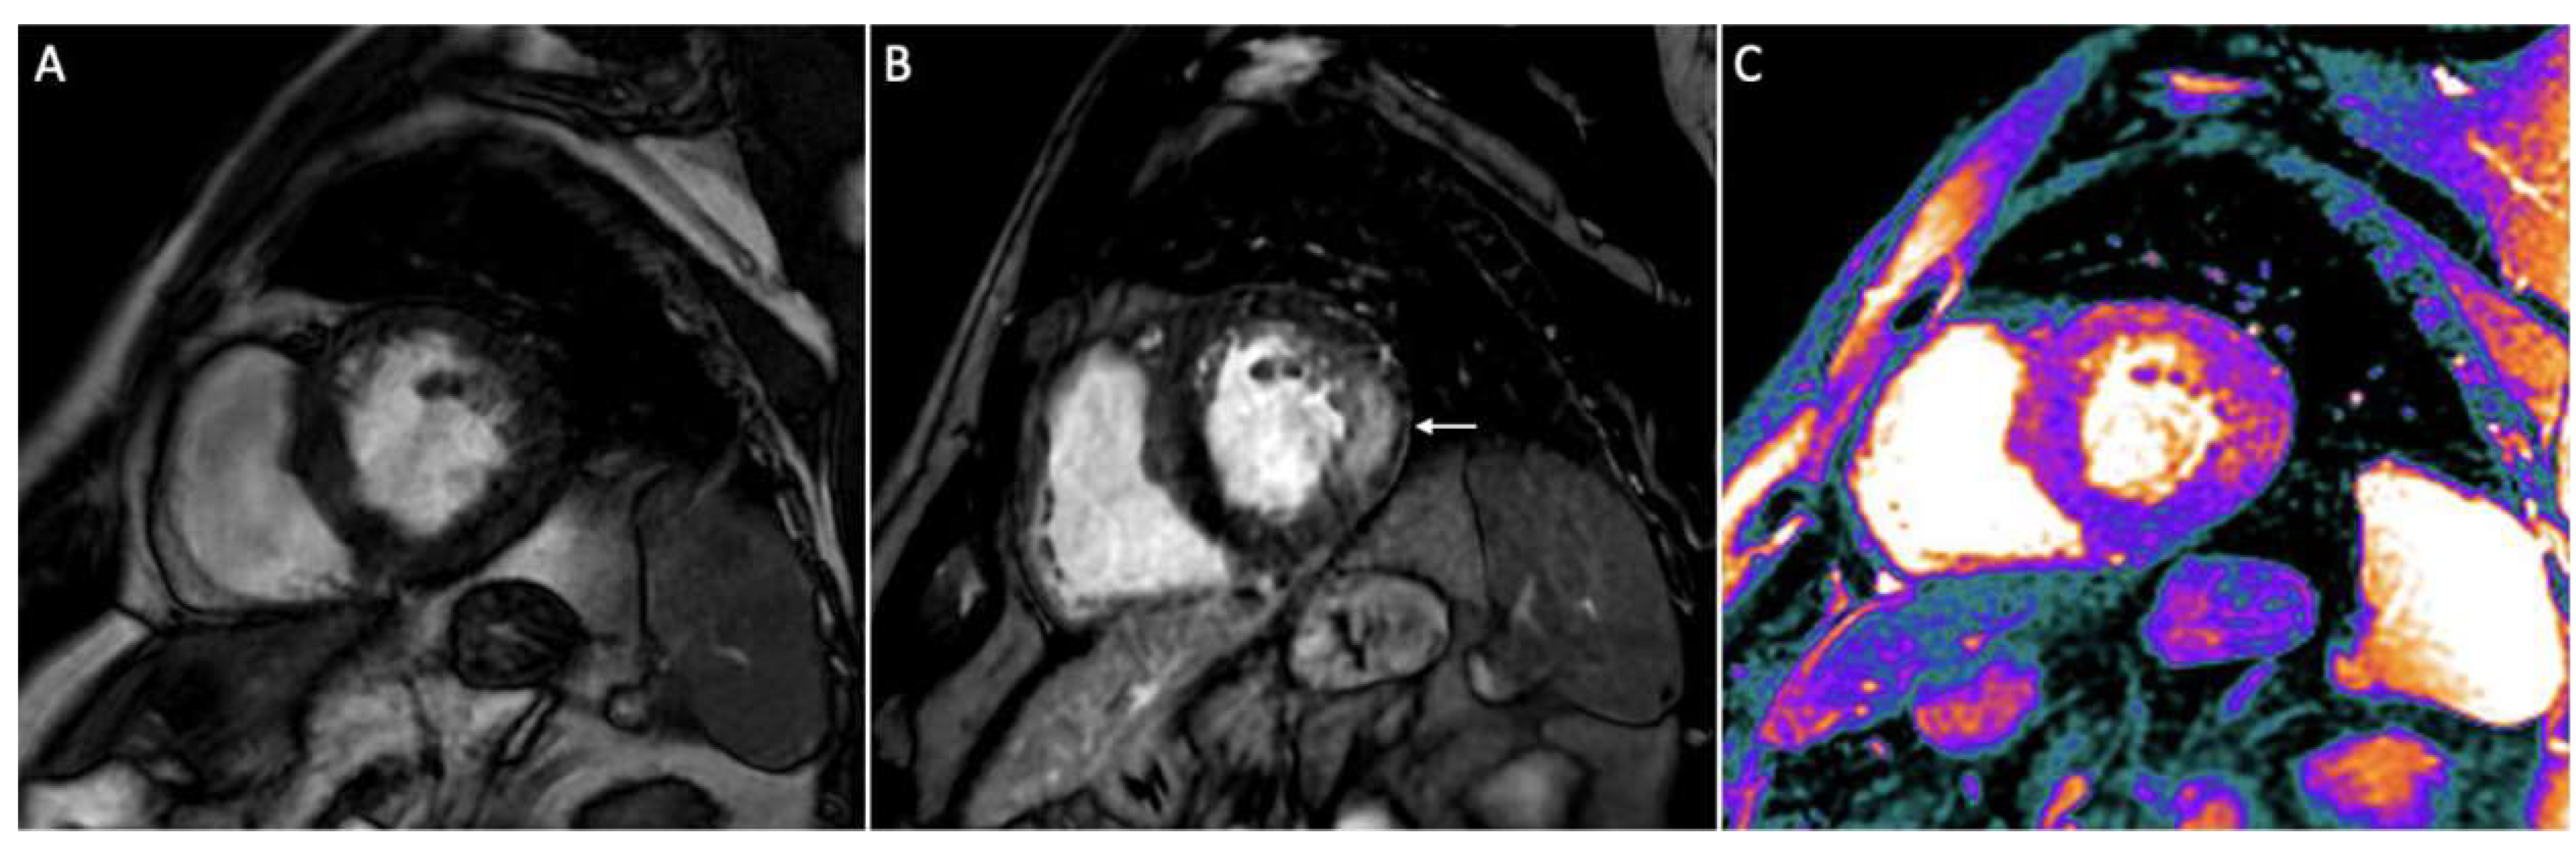

3.6. Infiltrative Cardiomyopathies

- Garcia-Pavia, P.; Rapezzi, C.; Adler, Y.; Arad, M.; Basso, C.; Brucato, A.; Burazor, I.; Caforio, A.L.P.; Damy, T.; Eriksson, U.; et al. Diagnosis and treatment of cardiac amyloidosis: A position statement of the ESC Working Group on Myocardial and Pericardial Diseases. Eur. Heart J. 2021, 42, 1554–1568. [Google Scholar] [CrossRef]

- Dorbala, S.; Ando, Y.; Bokhari, S.; Dispenzieri, A.; Falk, R.H.; Ferrari, V.A.; Fontana, M.; Gheysens, O.; Gillmore, J.D.; Glaudemans, A.W.J.M.; et al. ASNC/AHA/ASE/EANM/HFSA/ISA/SCMR/SNMMI Expert Consensus Recommendations for Multimodality Imaging in Cardiac Amyloidosis: Part 1 of 2-Evidence Base and Standardized Methods of Imaging. Circ Cardiovasc. Imaging 2021, 14, e000029. [Google Scholar] [CrossRef]

- Fontana, M.; Banypersad, S.M.; Treibel, T.A.; Maestrini, V.; Sado, D.M.; White, S.K.; Pica, S.; Castelletti, S.; Piechnik, S.K.; Robson, M.D.; et al. Native T1 mapping in transthyretin amyloidosis. JACC Cardiovasc. Imaging 2014, 7, 157–165. [Google Scholar] [CrossRef]

- Karamitsos, T.D.; Piechnik, S.K.; Banypersad, S.M.; Fontana, M.; Ntusi, N.B.; Ferreira, V.M.; Whelan, C.J.; Myerson, S.G.; Robson, M.D.; Hawkins, P.N.; et al. Noncontrast T1 mapping for the diagnosis of cardiac amyloidosis. JACC Cardiovasc. Imaging 2013, 6, 488–497. [Google Scholar] [CrossRef]

- Kotecha, T.; Martinez-Naharro, A.; Treibel, T.A.; Francis, R.; Nordin, S.; Abdel-Gadir, A.; Knight, D.S.; Zumbo, G.; Rosmini, S.; Maestrini, V.; et al. Myocardial Edema and Prognosis in Amyloidosis. J. Am. Coll. Cardiol. 2018, 71, 2919–2931. [Google Scholar] [CrossRef]